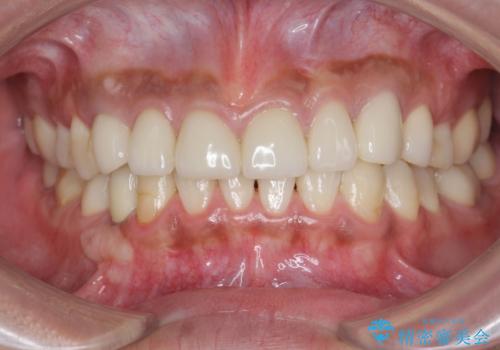

複数箇所コンポジット充填された前歯をセラミック治療

充填部位が大きく、再度充填をするには神経と近くなり抜髄のリスクが高まるため、劣化の少ないセラミックでフルカバーするセラミッククラウン治療を行うこととしました。

- 79.2万円(ジルコニアクラウン×6・仮歯×6)費用は治療当時の料金となります